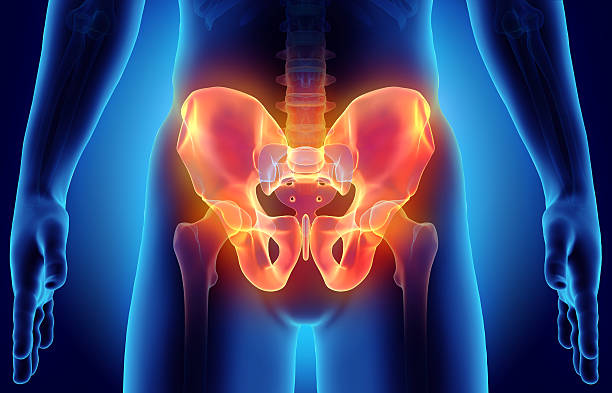

골반 통증은 오랫동안 앉아 일을 하는 현대 사회에서 흔히 발생하는 문제 중 하나입니다. 이 글에서는 골반 통증의 다양한 원인과 대처법에 대해 자세히 알아보겠습니다.

우리 몸에 통증이 발생하는 위치가 있는데요. 그 위치에 따라서 원인이 다르다고 합니다.

그래서 그 정확한 통증 위치를 파악하는게 중요한데요.